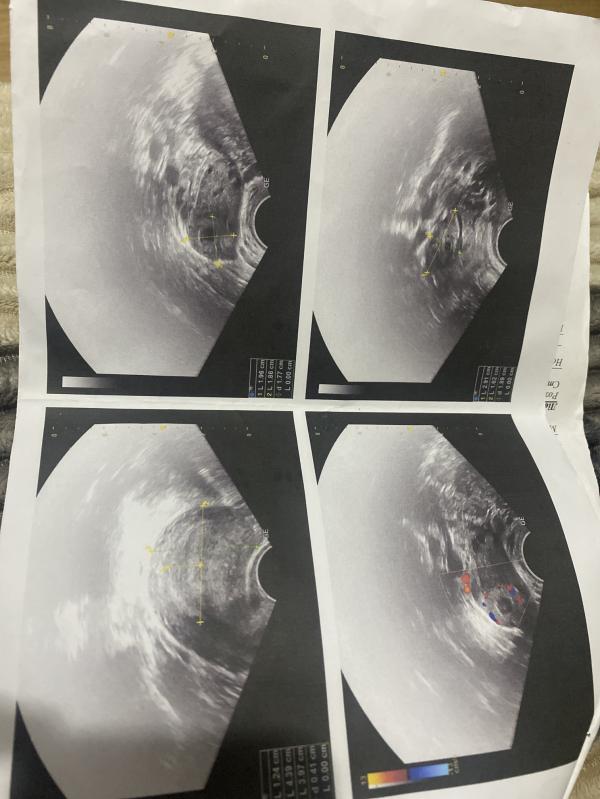

Была на узи,сказали что не нашли плод в матке,нашли какое-то желтое тело возле правого яичника , может ли это быть внематочная? Очень переживаю, и тесты не сильно насыщенные, вчера пришли результаты хгч 138( #першийзапис

Делала Узи в 4-5 недель, было видно желтое тело и беременность. Вы рано пришли)) подождите пару недель

Жёлтое тело должно быть обязательно и чем больше, тем лучше (15 мм и больше) - это ваш лопнутый фолликул, после овуляции и оно будет пока плацента не начнётся функционировать до недели 15 по-моему, уже не помню и оно вырабатывает прогестерон для поддержки малыша

«желтое тело» свидетельствует об овуляции, соответсвенно в этот период высоки шансы забеременеть. если оно не уменьшается в определенный цикл, то значит оплодотворение прошло. просто совсем маленький срок еще.

Желтое тело и должно быть,оно сохраняет беременность,вырабатывая прогестерон.Образуется на месте лопнувшего фолликула

А для визуализации плода в полости срок маленький,пересдайте хг,чтобы отследить динамику

А желтое тело,и должно быть,оно возникает после овуляции и отвечает за сохранение беременности если она наступила,так как выделяет гормон прогестерон

Какая задержка у вас? При таком уровне ХГЧ даже хороший специалист не увидит беременность. Если речь о кисте желтого тела, то она часто появляется во время беременности и не несет никакой угрозы. ХГЧ сдать в динамике. Повторно на УЗИ с результатом ХГЧ от 1500 и выше